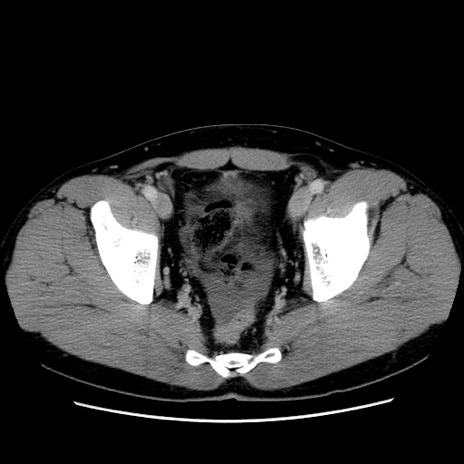

症例4(横断像)

【症例】30歳代男性

【主訴】腹痛、嘔吐

【現病歴】昨晩から突然の腹痛あり、その後嘔吐、軟便も出現。腹痛が改善しないため救急搬送となる。2日前にしめ鯖の食事歴あり。

【身体所見】意識清明、苦悶様、BP 135/90mmHg、BT 35.7℃、腹部:平坦、やや硬、心窩部〜臍部に自発痛、圧痛あり、筋性防御+、反跳痛-

【データ】WBC 8100、CRP 0.57